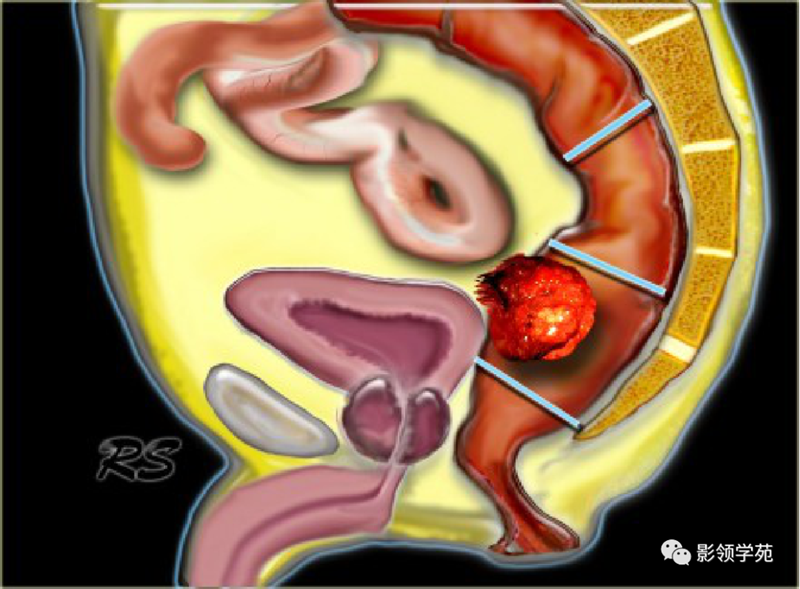

1、影像学检查:如X线胃肠道钡餐造影、CT检查、MRI检查、经直肠超声检查。腹部X线检查适用于伴发急性肠梗阻病人,可见梗阻部位上方的结肠有充气胀大现象。直肠癌术前行直肠MRI为常规检查项目,是术前分期的重要依据。

直肠癌CT